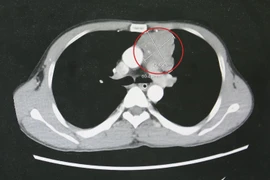

Tìm lại hy vọng sống cho thanh niên 39 tuổi hôn mê, co giật do nhược cơ

Nhược cơ là một loại bệnh tự miễn dịch dẫn đến rối loạn dẫn truyền tại các điểm nối thần kinh - cơ làm giảm chức năng hoạt động của hệ cơ.